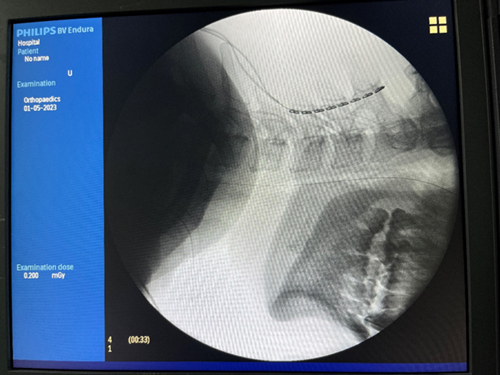

术中显示电极位置放置良好

许尚臣主任医师表示,脊髓电刺激术属于神经调控技术疗法之一,是将电极植入椎管内,以脉冲电流刺激脊髓神经治疗疾病的先进手段。脉冲刺激经上行网状激活系统传至大脑皮层,可改善脑循环代谢,调节局部脑血流,令大脑皮层兴奋,增强意识冲动及脑电活动。